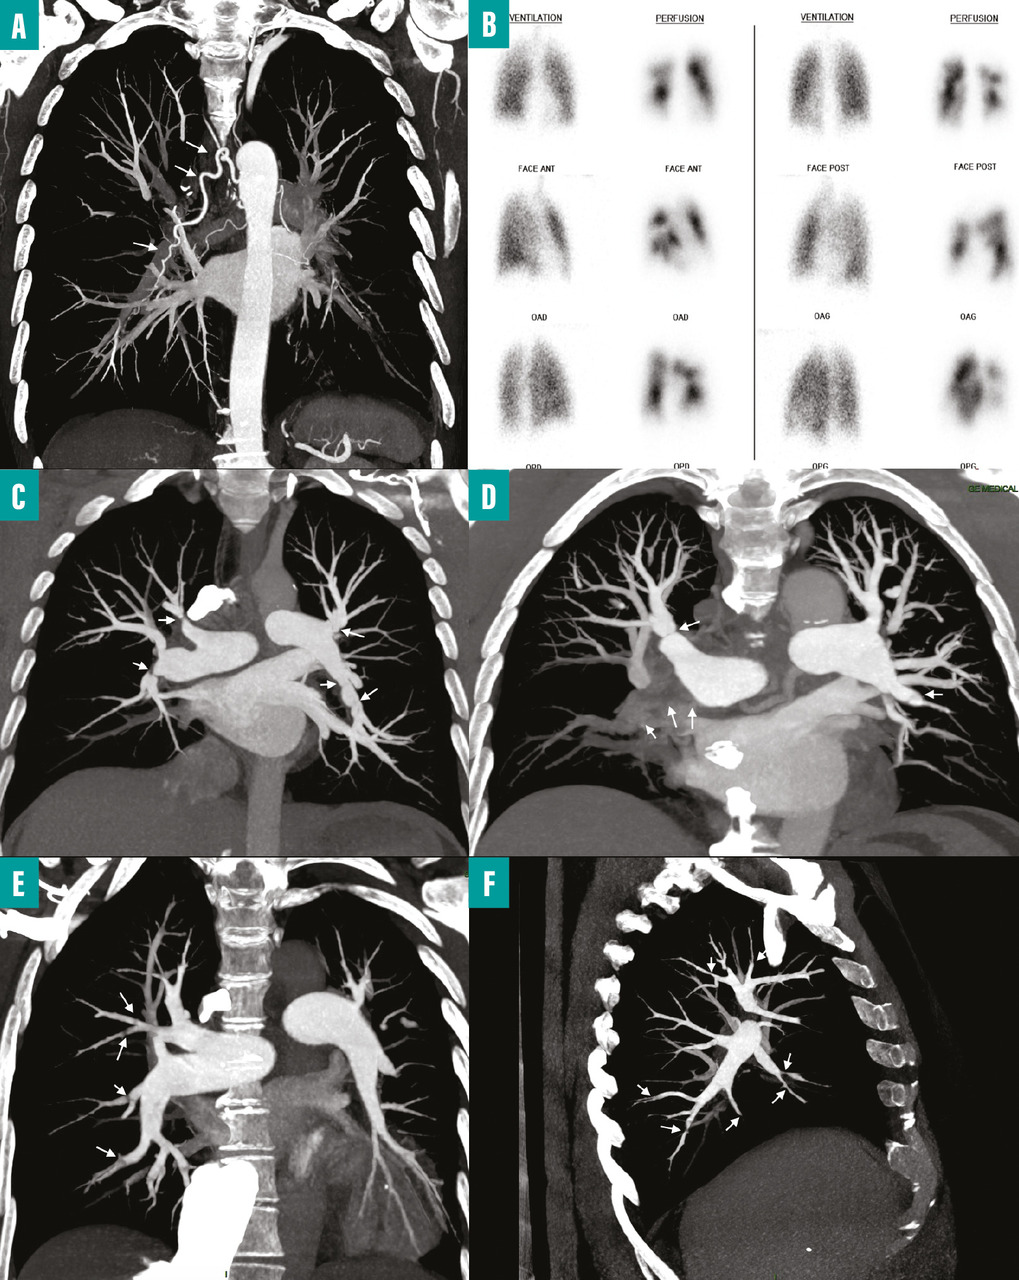

fig. 1B ) et une échographie cardiaque transthoracique afin de rechercher une HTP. En cas de probabilité intermédiaire ou élevée d’hypertension pulmonaire sur l’échographie cardiaque et d’anomalies de la perfusion pulmonaire sur la scintigraphie, il est recommandé d’adresser le patient à un centre de compétence de l’HTP pour confirmer le diagnostic d’HTP-TEC.

- au moment du diagnostic d’une EP, chez les patients qui ont une PAPs supérieure à 50 à 60 mmHg et/ou des lésions spécifiques d’embolie pulmonaire chronique associées aux signes d’EP aiguë sur l’angioscanner thoracique (

- d’anomalies de la perfusion pulmonaire associées à une ventilation normale (défauts de perfusion non concordants) sur une scintigraphie pulmonaire de ventilation/perfusion ;

- de lésions thromboemboliques chroniques sur un angioscanner thoracique et/ou une angiographie pulmonaire.

L’endartériectomie pulmonaire demeure le traitement de référence chez les patients opérables (fig. 1C-D ). L’évaluation de l’opérabilité repose sur l’accessibilité des lésions à cette chirurgie ainsi que sur la présence ou l’absence de comorbidités significatives. Les lésions sont considérées comme accessibles à une endartériectomie pulmonaire lorsqu’elles se situent au niveau tronculaire, lobaire ou segmentaire proximal.

La prise en charge interventionnelle par angioplastie artérielle pulmonaire concerne classiquement les patients avec une atteinte non accessible à la chirurgie (lésions segmentaires et sous-segmentaires) [fig. 1E-F ]. Cette technique endovasculaire, développée initialement au Japon, utilise des ballonnets de différents calibres pour dilater les lésions obstructives, telles que les sténoses des artères pulmonaires.17